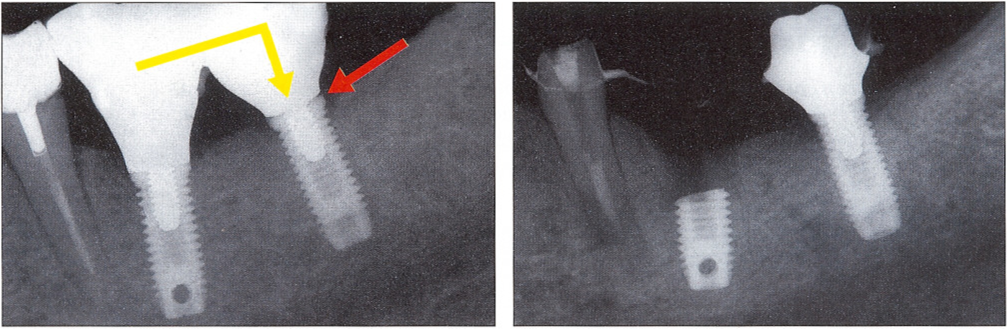

Исследование на рентгене после имплантации зубов

Раздел: Снимки-откровения